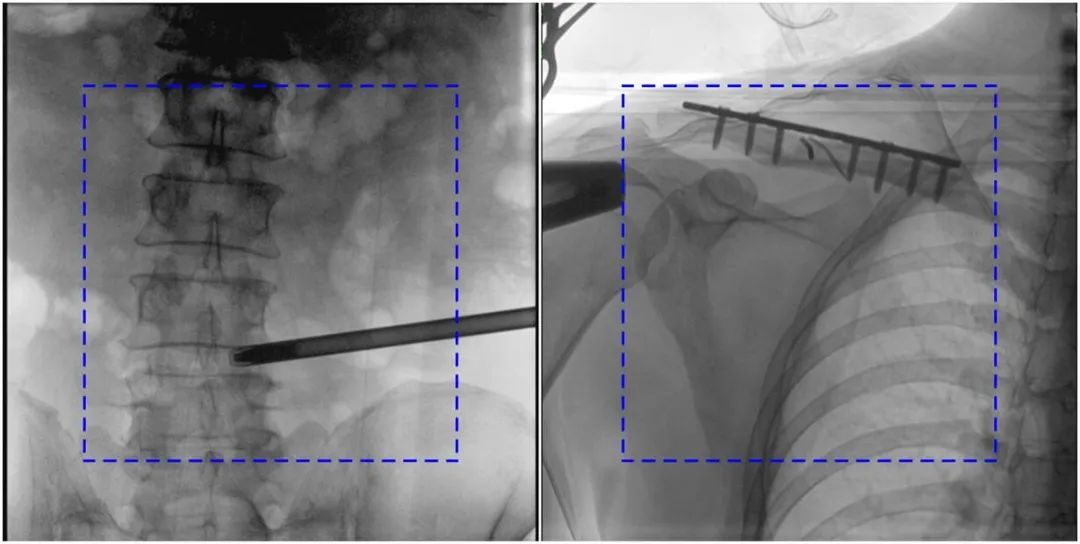

與傳統(tǒng)的21CM×21CM成像尺寸相比,普愛(ài)醫(yī)療大平板一體式C形臂具有30CM×30CM更大成像尺寸,能夠一次成像5.5節(jié)椎體,呈現(xiàn)更全面的影像信息,即便是手術(shù)經(jīng)驗(yàn)不豐富的年輕醫(yī)生也能通過(guò)圖像迅速判斷椎體節(jié)段、定位手術(shù)部位,避免因?yàn)橐曇安蛔愣斐傻亩啻味ㄎ?、反?fù)曝光,提高效率的同時(shí)避免過(guò)量攝入輻射。

普愛(ài)醫(yī)療大平板一體式C形臂圖像與傳統(tǒng)圖像對(duì)比(藍(lán)色虛線(xiàn)內(nèi)為傳統(tǒng)21CM×21CM平板的成像區(qū)域)